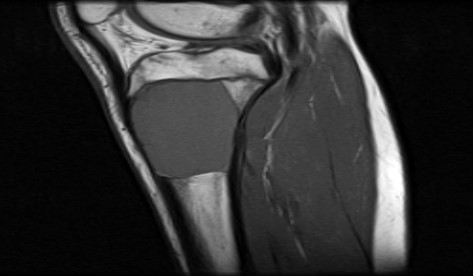

- Xray:

- Eccentric radiolucent lesion with expansile remodeling, involving the metaphysis of long bones

- Finger in the balloon sign possible (Orthop Traumatol Surg Res 2015;101:S119)

- MRI:

- Multiloculated cyst with characteristic fluid-fluid levels

Radiology images